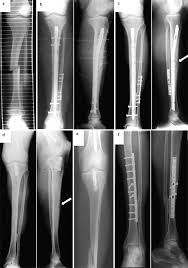

Bei den dabei verwendeten sogenannten Marknägeln handelt es sich meist um Implantate aus Titan oder Edelstahl. Die Diagnose Multiples Myelom in Deutschland fälschlicherweise oft mit dem solitären Plasmozytom gleichgesetzt löst Schock Angst und Ratlosigkeit aus. Es blieben subtrochantär große Löcher im Femur mit einer lateralen kortikalen Lücke von 12x12 mm und einer weiteren.

Immerhin wird das Bein bin zum Knochen geöffnet Gewebe und Muskeln durchtrennt und es verbleiben Löcher in den Knochen. Die Schraube im Schenkelhals ließ sich noch lösen die zwei Verriegelungsschrauben jedoch nicht - die Schraubenköpfe brachen ab die Gewinde wurden überbohrt und brachen wieder ab. Da die Drähte bei auch nur leichter Lockerung eine Gefahr für Strecksehen darstellen gibt es sehr gute Gründe die Kirschnerdrähte zu entfernen.

Pdf Rekonstruktion Nach Unterschenkelfehlheilung